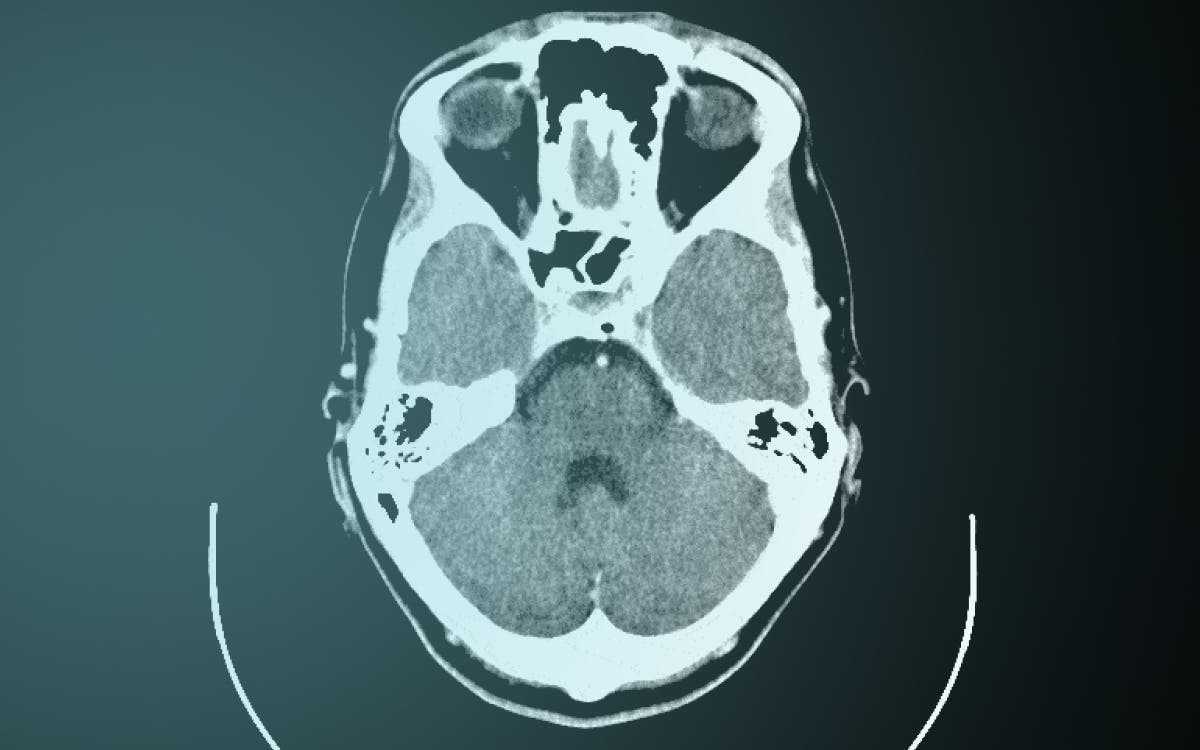

Representations of the corpse have transfixed society since antiquity. Whether visualised in portraiture or vanitas, embodied in effigies or death masks, or recorded on photographs or x-rays, the dead can only appear to the living through their images.

It has been suggested by philosophers, anthropologists, sociologists, and legal scholars that images enable the corpse to appear and speak to the living. The practice of visualising the corpse has shaped an inventory of techniques for representing death in the domains of art, medicine and law. In a world where death touches us in many ways, from playing cards to horror films, public executions to coronial investigations, images of the corpse remind us that the dead never disappear. Whether they are memorialised in art, pathologised in medicine, misrepresented in law or simply linger in the empty spaces of galleries, hospitals or courtrooms, the corpse always remains at work.